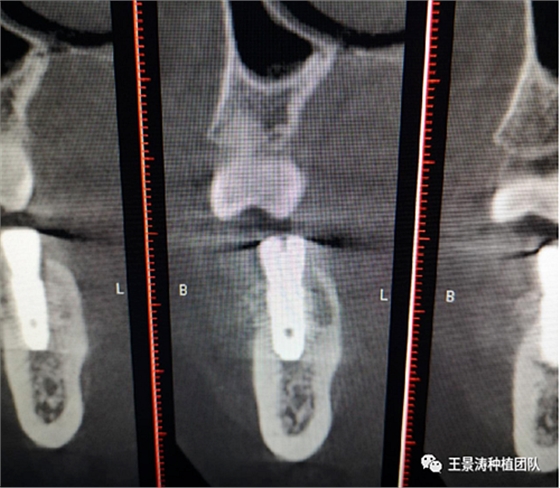

下述病例則是15區(qū)域的即刻種植,15因牙冠折斷于齦下,無法樁核冠修復(fù),則考慮種植修復(fù)。但拍攝CBCT后發(fā)現(xiàn)根尖距上頜竇底距離較短?;颊邽槟贻p女性,無全身系統(tǒng)疾病且可利用上頜竇底與根尖皮質(zhì)骨雙側(cè)皮質(zhì)骨固位,且此位置可通過頰側(cè)軟組織減張技術(shù)獲得嚴(yán)密封閉牙槽窩。因其根尖距上頜竇距離較低,遂拔除15后行上頜竇內(nèi)提升,埋入式種植,最終修復(fù)的完成。